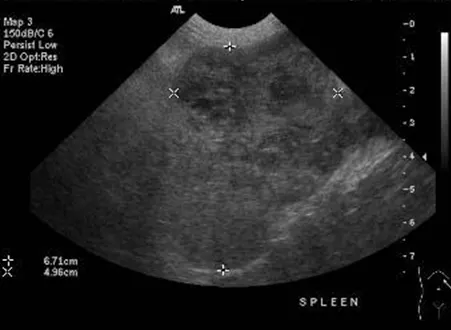

FIGURE 1

Ultrasound image of a splenic mass with a mixed echogenic pattern consistent with blended heterogeneous tumor and fluid-filled (blood) cavities in the splenic parenchyma